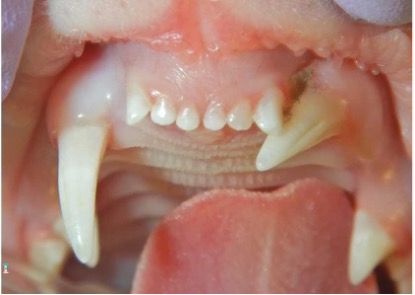

• Brachiocephalic felines: Persians, British shorthairs, and exotic shorthairs often exhibit abnormally positioned teeth due to crowding associated with the brachiocephalic skull shape. (Figure 7)

• Brachiocephalic canines: Dogs with brachiocephalic skull shapes experience crowding and rotated teeth, leading to advanced PD. Additionally, unerupted teeth (Figure 8) in these breeds may result in dentigerous cysts if left untreated.